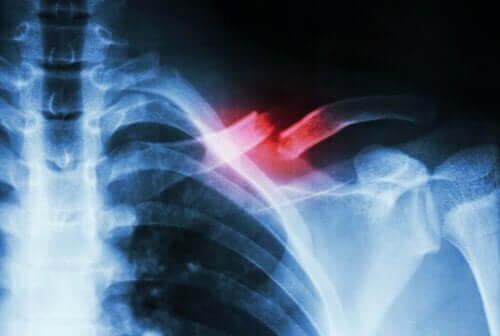

どこで起こる?疲労骨折の原因と症状

一般的に、疲労骨折は反復運動や、運動や活動の量や強度が急激に増加することが原因で起こります。

疲労骨折が起こると強い痛みを伴い、疲労骨折をしている骨がずれることもあります。

疲労骨折とはなんですか?

疲労骨折は、運動など身体活動による過負荷の結果として発生する可能性があります。